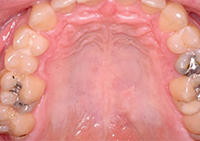

What is VELscope Vx?

- The VELscope Vx helps discover oral disease BEFORE it can be seen under ordinary light

- The VELscope Vx exam is quick, painless, and effective